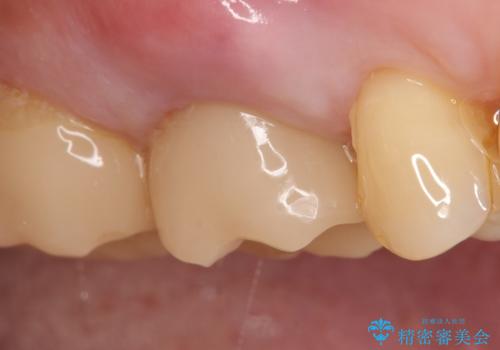

オールセラミッククラウン 根管治療後の補綴

オールセラミッククラウン(エコノミー)はスタンダード以上と違い、一塊となっているため欠けてしまうリスクが低いのが特徴です。

しかしその反面選択できる色の種類が少なく、色合いも単調であるという欠点もありますが、今回のケースのように前後の歯がクラウンの場合などでは十分に審美的な補綴が可能となります。